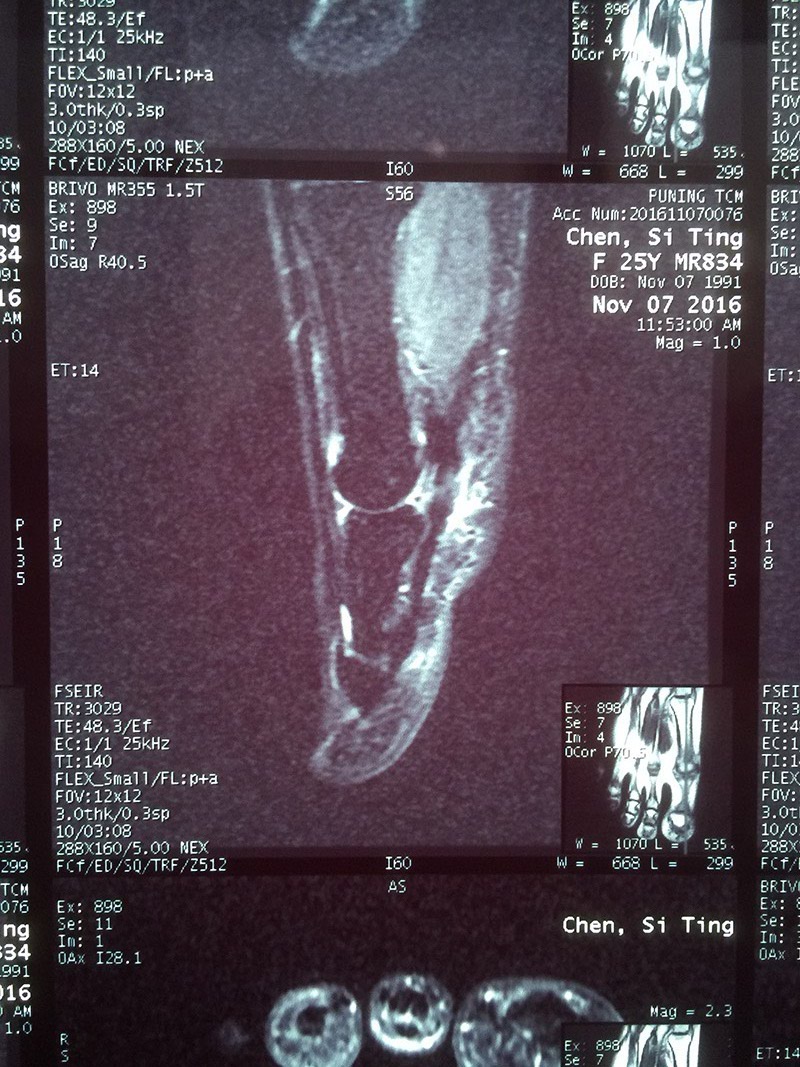

11月7日前往当地某中医院住院治疗,院内行右足脚趾MR提示:局部软组织水肿,血沉、血常规、C反应蛋白均提示无明显异常,医生给的诊断是肌腱炎,于是又继续抗感染治疗6天,陈小姐依然还是感觉大趾底部刺痛,行动不便。